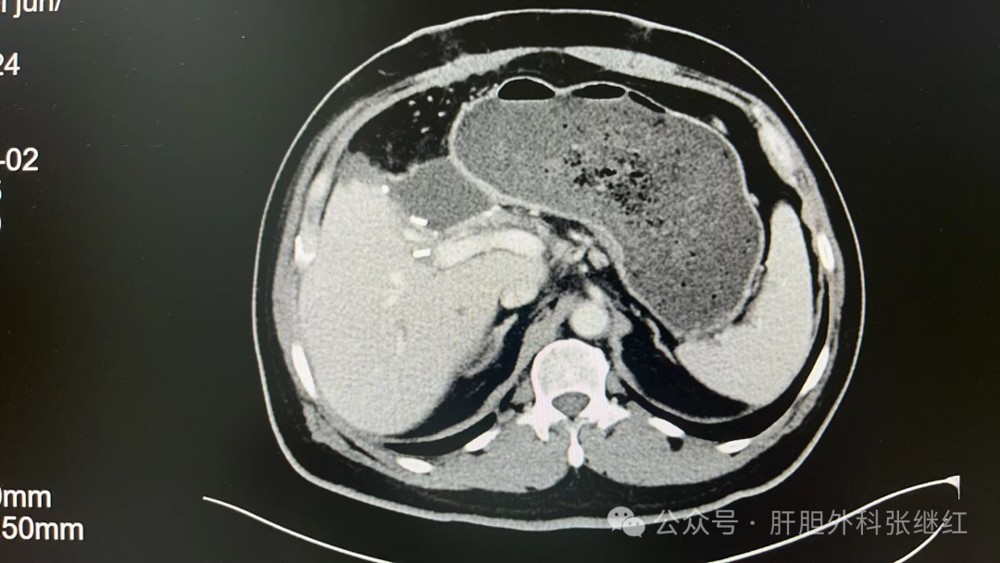

转化治疗前CT

该患者是佛山复星禅诚医院肝胆胰外科病例,张继红医生有幸参加了术前多学科会诊和手术。1年前,一男性56岁病人,经CT、MR等影像学检查和病理活检确诊为胆管细胞癌,瘤体巨大,长径超过10厘米,且伴门静脉左支癌栓形成和多发腹腔淋巴结转移,经多学科会诊后决定应用吉西他滨和奥沙利铂化疗联合PD-L1单抗(度伐利尤单抗)免疫治疗进行转化治疗后再手术切除。经上述化疗联合免疫治疗五个疗程(每次均为单次给药,间隔时间21天)治疗后肿瘤明显缩小,直径约5厘米,淋巴结病灶也有所减少或缩小,达到了影像学部分缓解和手术切除的标准,经多学科会诊后决定行扩大左半肝切除及区域淋巴结清扫术,术后再行辅助治疗。本为腹腔镜手术,术中见左肝肿瘤萎缩明显,肿瘤压迫右侧肝蒂,肝门部及肝总动脉周围未见明显肿大淋巴结,肝门部粘连严重,仅清扫12a、12b、7-9组淋巴结所在区域脂肪淋巴组织,解剖离断左肝动脉、门静脉左支及左肝管,发现肿瘤基本位于缺血范围内,超声引导下在缺血线和S5段肿瘤外侧画切肝线,拟切除包括胆囊的S5段和左半肝,15+5min模式间歇性阻断肝门,沿预切线离断肝实质,达右肝蒂时发现肿瘤紧贴右肝蒂,为避免右肝蒂损伤,中转开腹完成整块切除包括胆囊的S5段及左半肝。手术后病理证实肿瘤100%坏死,清扫淋巴结亦未发现肿瘤细胞,达到病理学完全缓解(pCR)。术后早期肝断面少许积液,经引流后积液消失。目前病人状态良好,已无瘤生存半年余。